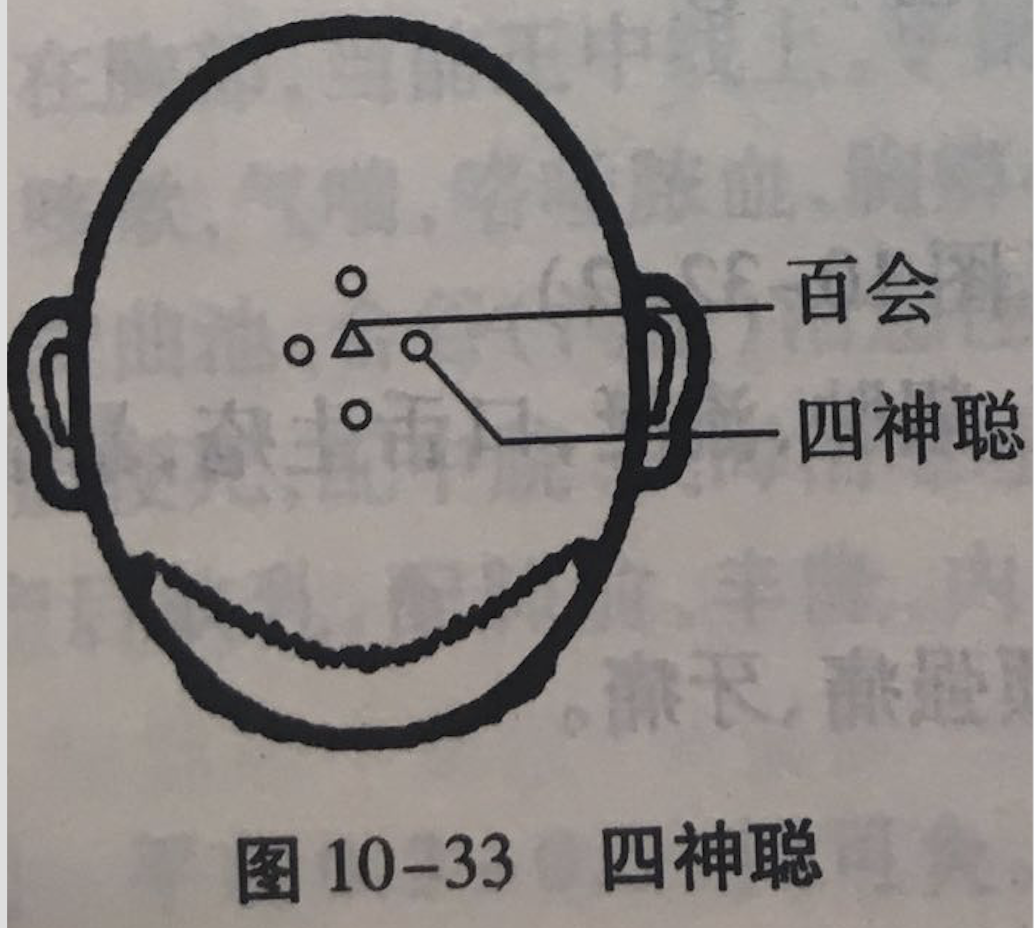

四神聪

【定位】 在头顶部,当百会前后左右各 1 寸,共 4 穴(图 10-33)。

【主治】 头痛,眩晕,失眠,健忘,癫狂,痫证,偏瘫,脑积水,大脑发育不全。

【刺灸法】 平刺 0.5 ~ 0.8 寸;可灸。